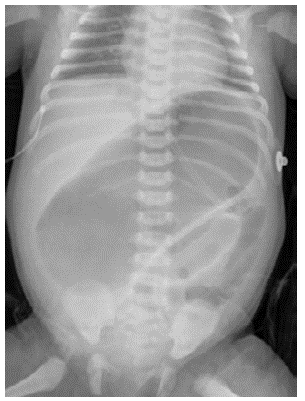

On admission at HOMI, the patient presented with markedly distended abdomen (Figure 1) with absent bowel sounds, normal position of the anus and no genital abnormalities.

Invasive ventilation was initiated and a nasogastric tube was passed in-situ. An abdominal x-ray showed a large dilated loop of bowel (Figure 2), without a double bubble sign, ruling out duodenal atresia. Based on those findings, in her third day of life, an exploratory laparotomy was performed. A right colon atresia type III (Grosfeld classification) 11 was identified, with a difference of proximal distal caliber from 10 to 1 (Figure 3). A derivative Hartmann's colostomy was performed, given the difference of caliber size that did not allow primary anastomosis. Rectal biopsies were taken, reporting ganglion cells and ruling out Hirschsprung's disease.